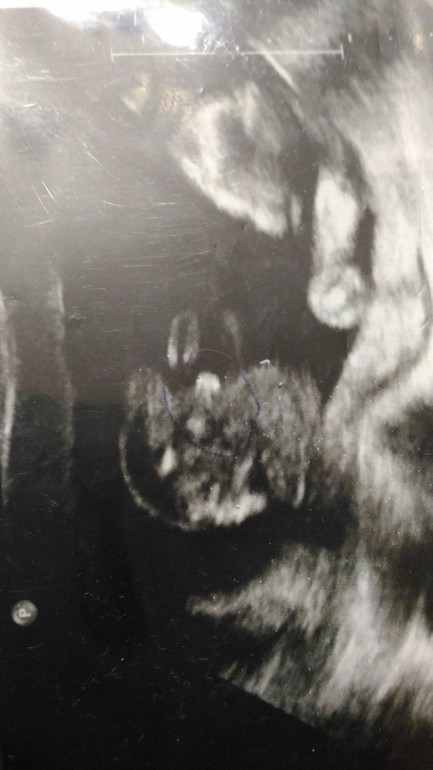

Вот наш сынок.

обведено ручкой синей, не знаю видно вам или нет.

Клиника платная, а на аппаратуре жалеют денег